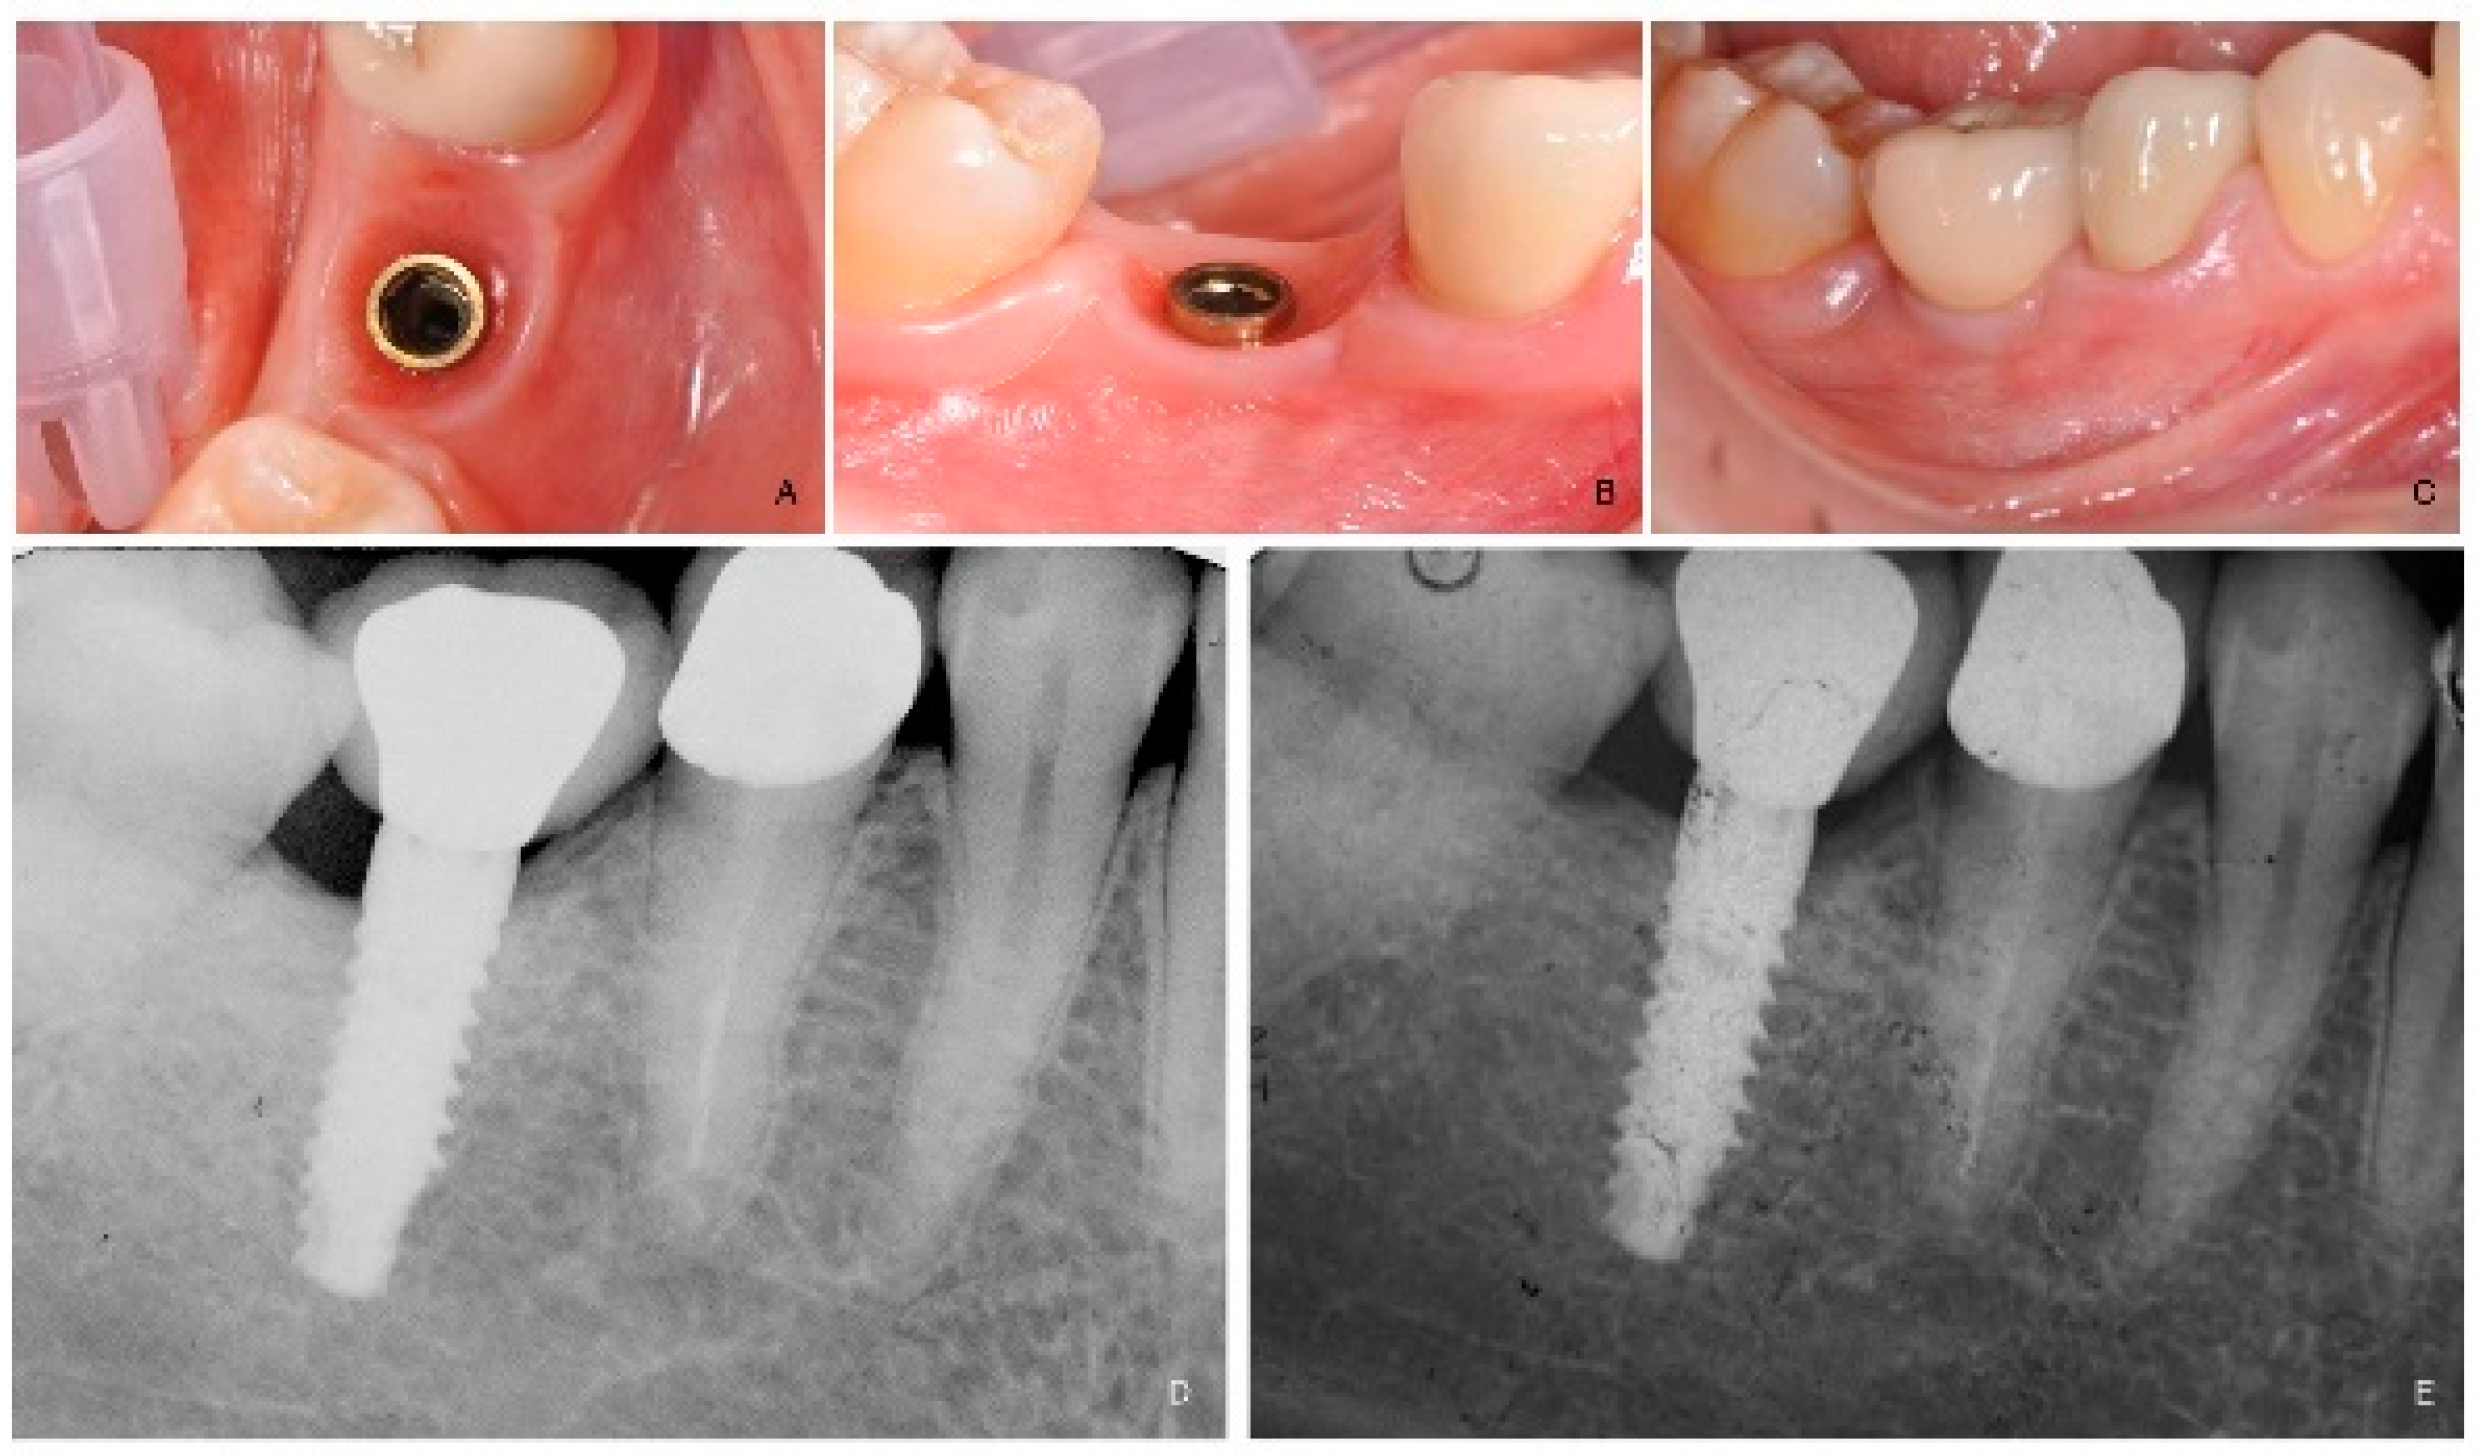

Four months after implant placement (Figure 3A,B), a customized open-tray impression with screw-retained transfer impression copings was taken at implant level using a polyether material (ImpregumTM, 3M ESPE, Seefeld, Germany). The screw-retained prosthetic crowns were delivered within a month. The occlusal surface was kept in slight contact with the opposite dentition. Periapical radiographs and clinical pictures of the study implants were taken, oral hygiene instructions were delivered, and patients were enrolled in a follow-up program. (Figure 3C–E).

Figure 3. (A): Intraoral occlusal view of the implant immediately before prosthesis delivery at tooth number 46. (B): Intraoral lateral view of the implant immediately before prosthesis delivery. (C): Intraoral lateral view at one year after loading follow-up. (D): Periapical radiograph at prosthesis delivery. (E): Periapical radiograph at one year after loading follow-up.